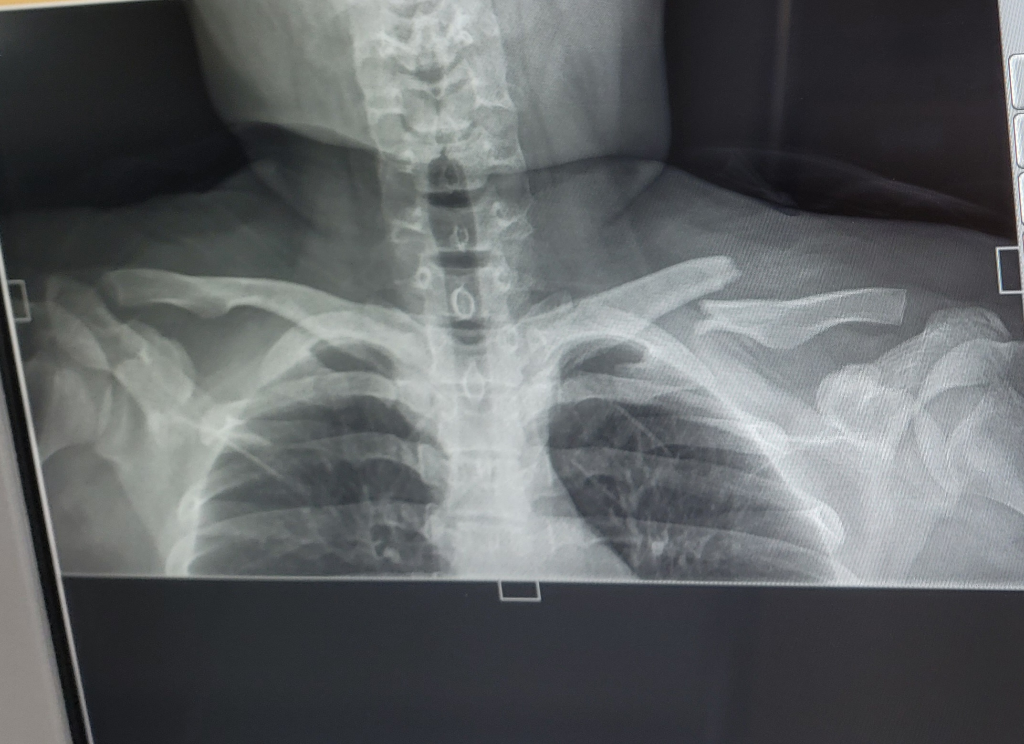

이정도로 부러졌습니다 전문적인 의사분들께 이 상황은 수술을 해야하는지 묻고싶습니다

쇄골이 이렇게 부러졌는데 수술 꼭 해야할까요? 정형외과 선생님분들 답장 부탁드립니다..너무 무섭고 통증도 있습니다 ㅜㅜ 도와주세요

무조건 수술하시는게 맞습니다.

쇄골이 완전히 분리된 상태이고 수술 안하시면 팔을 사용하시는데 문제가 생기실겁니다.